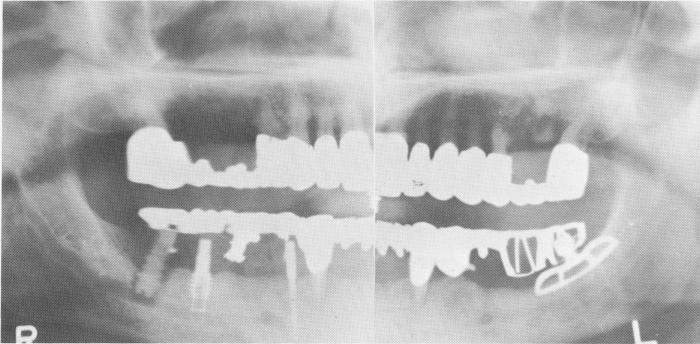

Fig. 14-7. The crystalline bone screw could be failing for two reasons other than poor design: it was screwed too deeply and could have sunk slightly through the superior wall of the mandibular canal, thus loosening the implant; or the hole made with the tap could have been too large, causing the failure.

Fig. 14-8. A broken posterior implant occurred by trying to screw it deeper while the bone resisted. Osteolysis is caused by insufficient depths of implant and not by the broken screw. (From Linkow, L. I.: Alloplastic implants. In Gold-man, H. M., Forrest, S. P., Byrd, D. L., and McDonald, R. E.: Current therapy in dentistry, vol. 3, St. Louis, 1968, The C. V. Mosby Co., pp. 335-356.)

The vent-plant, being self-tapping and stronger than the spiral-shaft implant because it is made of titanium rather than Vitallium, has much less chance of breakage when forced into position. Occasionally, however, vent-plants have broken (Fig. 14-9).

Another candidate for easy breakage is the narrow ridge implant (Fig. 14-10). If its site has not been properly prepared, it can be snapped while forcing it into the bone.

Fig. 14-9. The uprights joining the threads with the apical ring of the vent-plant broke during its insertion because of improper use of the helical burs. A helical bur was used that had a narrower diameter than the apical ring (thereby placing a great deal of pressure and torque on the ring) that was smaller in diameter than the outer diameter of the implant threads.